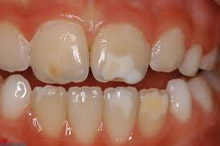

Υπενασβετίωση της αδαμαντίνης

Συνήθως εκδηλώνεται με λευκές, κίτρινες ή καφέ κηλίδες στους τομείς και τους γομφίους, μπορεί όμως να επηρεάσει και άλλα δόντια. Η κλινική εικόνα μπορεί να περιορίζεται μόνο στην εμφάνιση αυτών των κηλίδων, ή να είναι πιο σοβαρή προκαλώντας απώλεια της αδαμαντίνης του δοντιού, με συνέπεια την εμφάνιση ευαισθησίας και πόνου καθώς και τερηδόνας.

Η κατάσταση αυτή της αδαμαντίνης οφείλεται σε διαταραχή της διάπλασής της με αποτέλεσμα την ελλιπή ενσωμάτωση των μετάλλων στη δομή της. Έχουν ενοχοποιηθεί διάφοροι παράγοντες (περιβαλλοντικοί, ασθένειες της μητέρας και του βρέφους, διατροφή κ.ά.) οι οποίοι μπορούν να προκαλέσουν αυτές τις διαταραχές.

Σημαντική είναι η έγκαιρη διάγνωση από τον παιδοδοντίατρο και η εφαρμογή ενός ολοκληρωμένου προληπτικού προγράμματος προστασίας αυτών των δοντιών προκειμένου να διατηρηθούν υγιή.